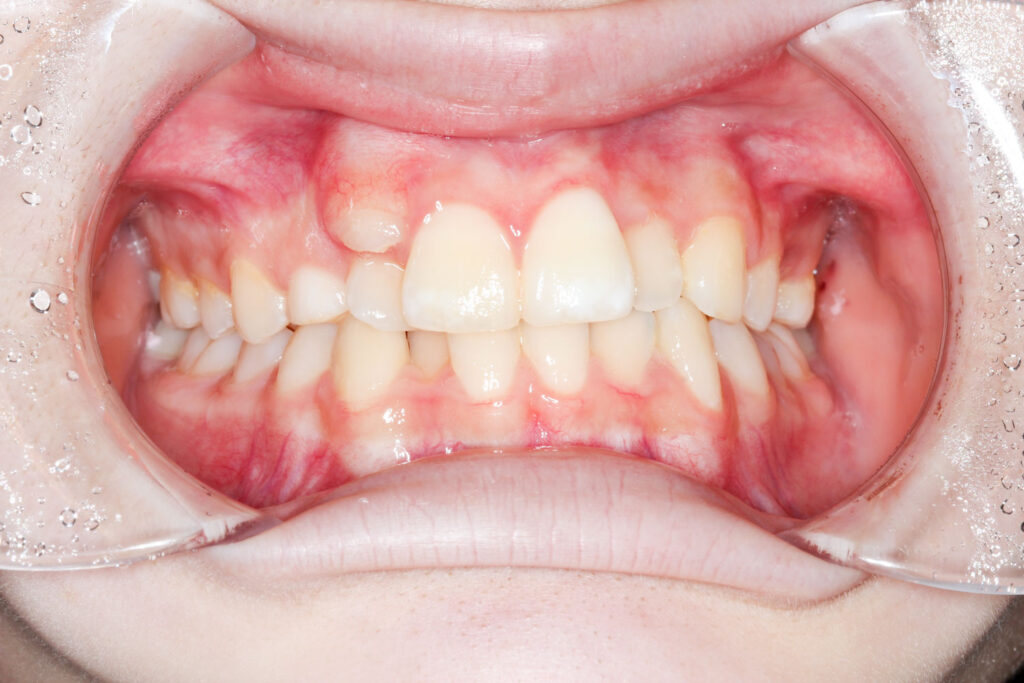

Before

After

年齢 10代

治療装置 上は裏側の矯正装置(フルリンガル)

治療内容 非抜歯

治療期間 2年8か月

リスク 歯の移動に伴う痛み、歯肉退縮、歯根吸収、歯肉炎、虫歯

主訴 ガタガタと隙間が気になる

症状 叢生と正中離開

治療回数 36回程度

総額費用 140万円程度